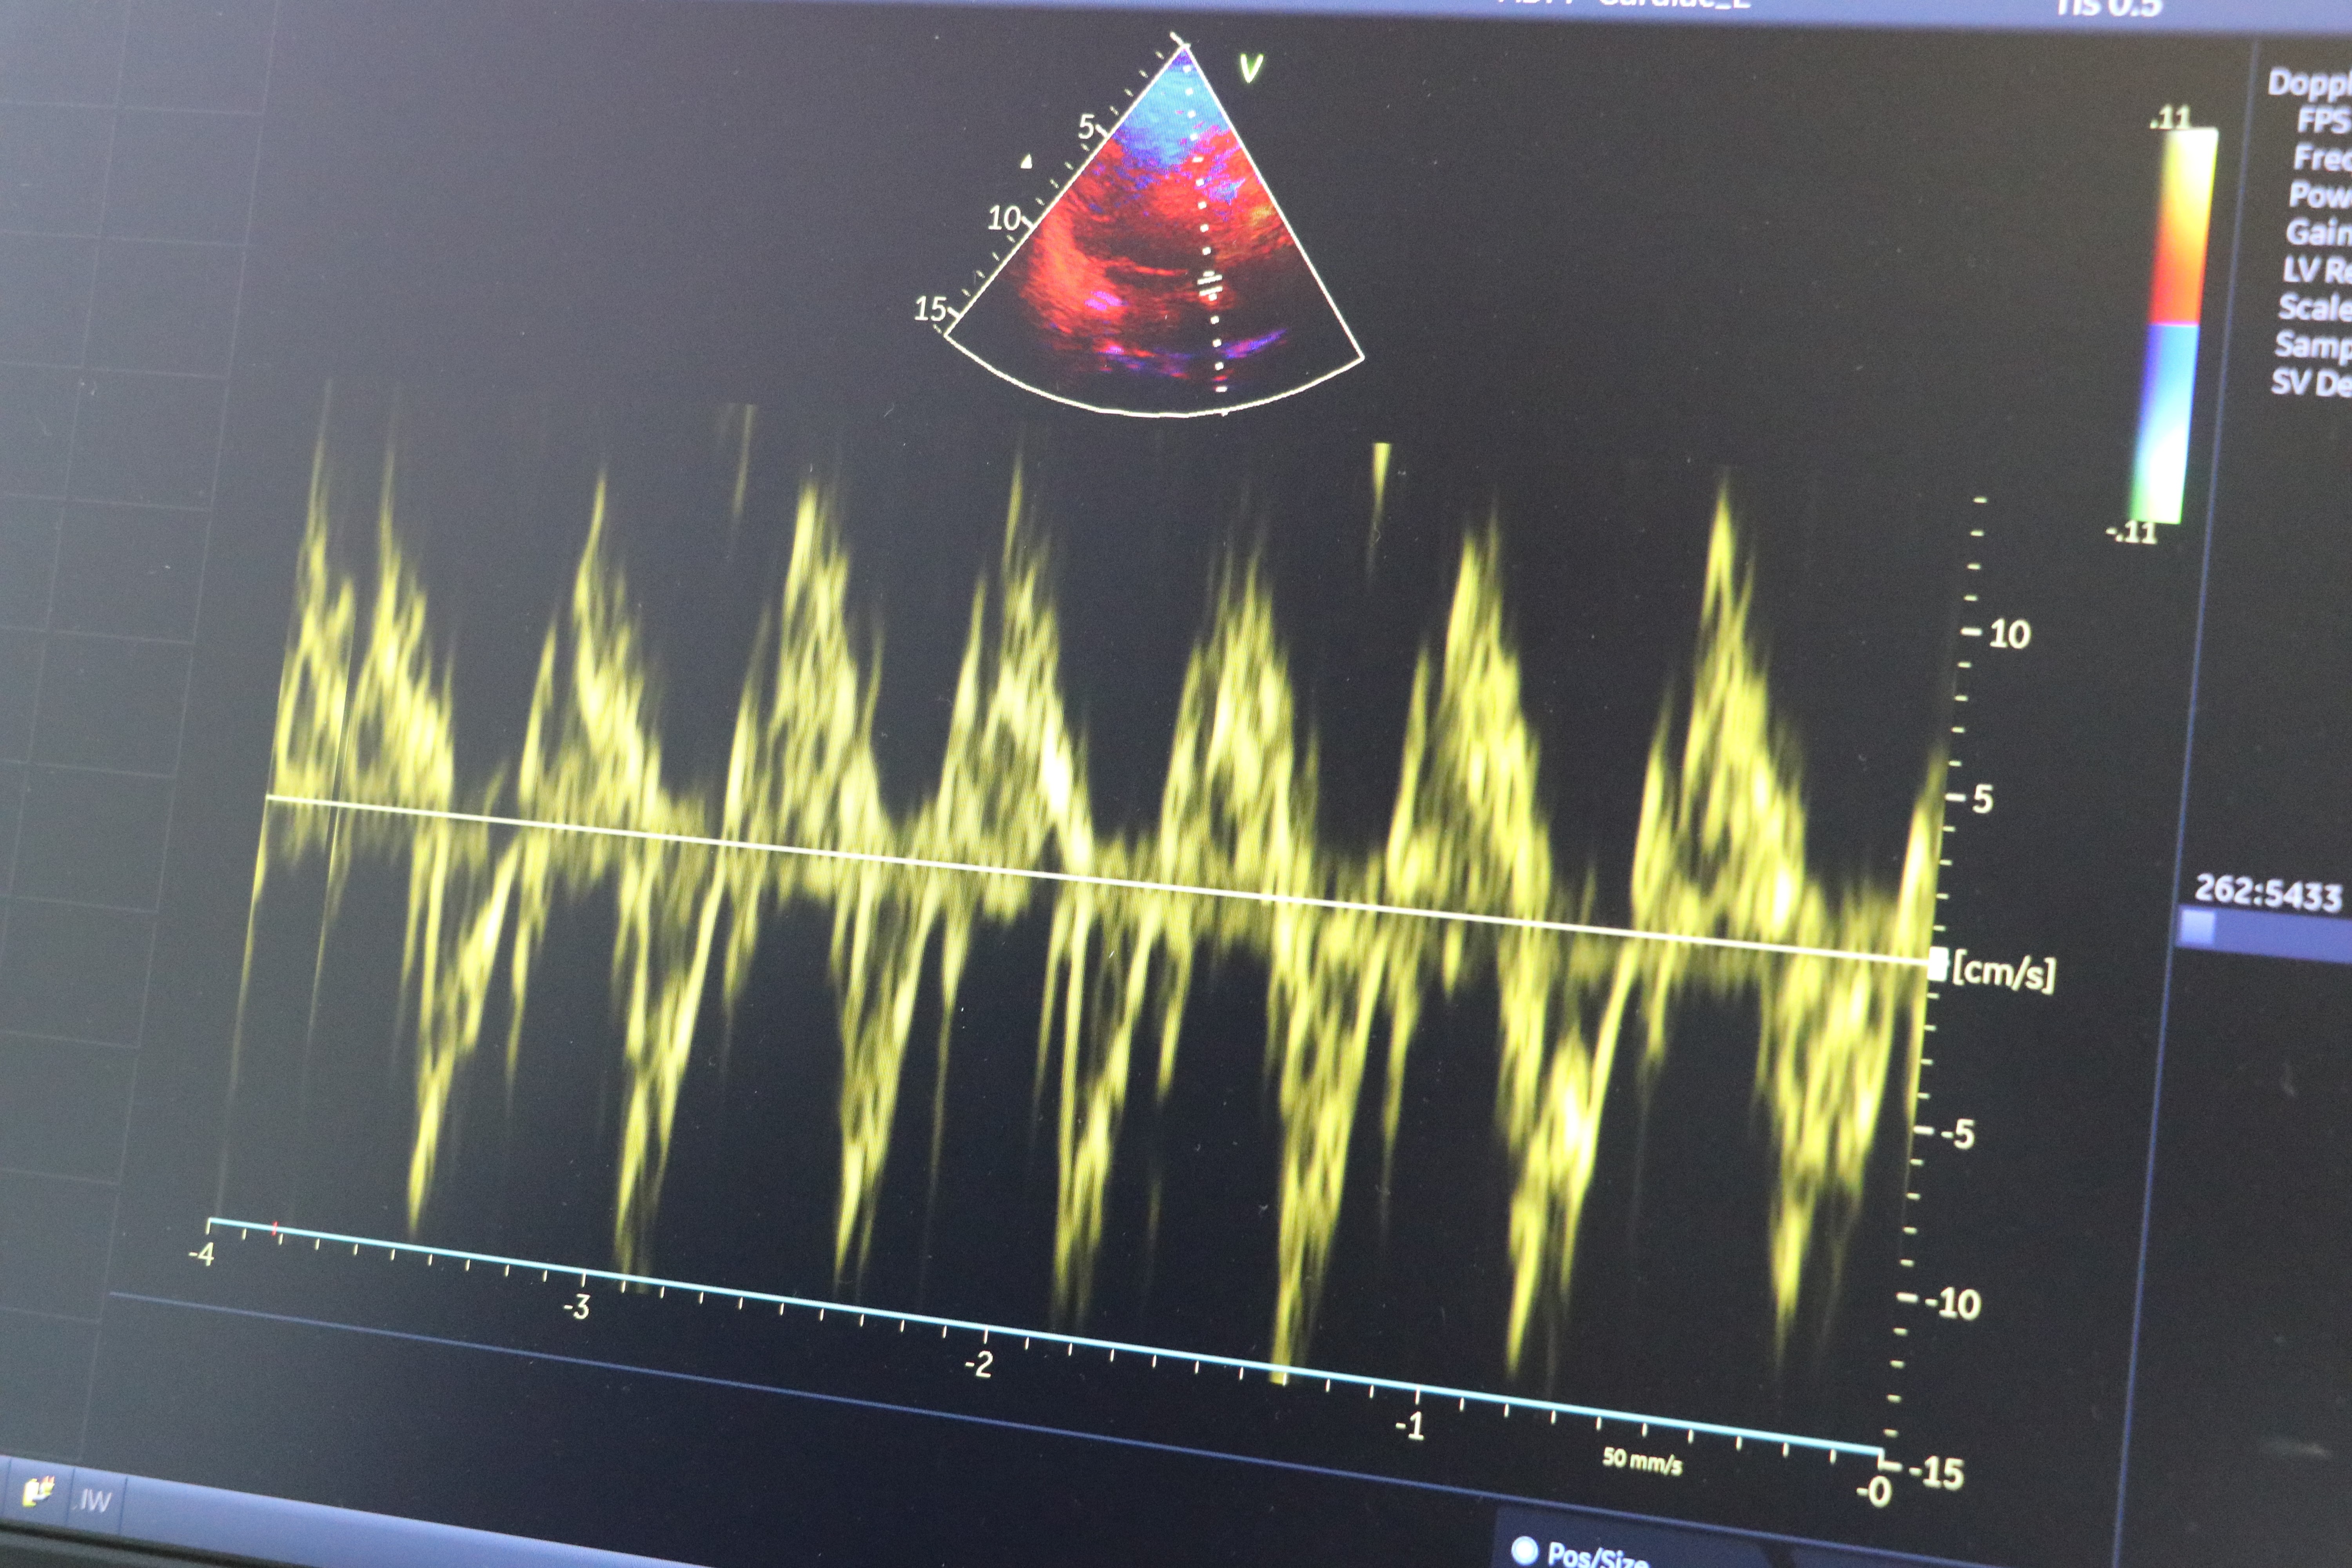

Kış aylarında kalp rahatsızlıkları olan hastaların beslenmelerine de dikkat etmesinin önemine vurgu yapan Yücel, " Kullandıkları ilaçları düzenli kullanıp doktor kontrolünü aksatmamaları gerekmektedir. Ayrıca soğuk havalarda sıvı alımı azaldığı için sıvı tüketimine dikkat etmeleri gerekmektedir. Soğuk havalarda vücut ısısını korumak önemli. Damarlarda kasılma, büzüşme (vazokonstriksiyon) oluşmakta ve kalp hızı artmakta, bu da soğuk havalarda dışarı çıktığımızda efor kapasitemizin azalmasına, nefes daralmasına ve göğüs ağrısına sebebiyet vermektedir. Beslenme noktasına da değinecek olursak, tuzlu ve yağlı gıdalardan uzak durmamız gerekmektedir. Tuz alımından sonra tansiyon yüksekliği kalbe yük oluşturmaktadır. Kanın yoğunluğunun artmasına bağlı olarak yağlı tüketimler kolesterol artışına sebebiyet vermekte, damarda plak oluşumuna ve kan akışının yavaşlamasına sebebiyet vermektedir. Yaz kış fark etmeksizin yağlı ve tuzlu gıdalardan kalp damar hastalığı olan kişilerin uzak durması gerekmektedir. Beslenme konusunda lifli gıdalar, bitki ve sebzeler tüketmemiz lazım. Balık tüketimi ve bol su tüketimine önem vermemiz gerekmektedir. Bunlara dikkat edilmediği durumlarda yeniden damar tıkanıklıkları oluşabilir, kalp spazmı dediğimiz hadiseler olabilir ve göğüs ağrısı oluşabilir. Kalp krizi, felç ve inme gibi durumlar tetiklenebilir. Kış aylarında kalp rahatsızlıkları olan hastalarımızın yaşamlarına ve beslenmelerine dikkat etmeleri, ilaçlarını düzgün kullanıp kontrollere önem vermeleri gerekmektedir" diye konuştu.